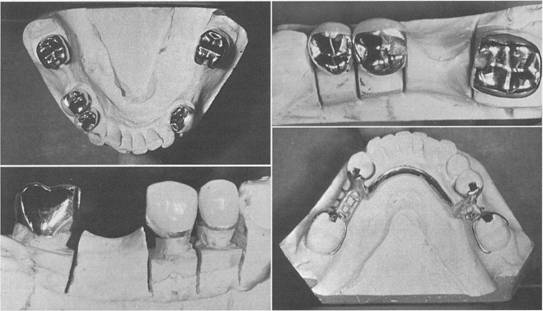

Fig. 6-13 Mandibular internal rest-supported partial denture. A, Abutment crowns with internal rests. Both dovetail design and gingival will prevent horizontal movement. H, Completed partial denture framework with cast lingual retention on all four abutments. Short buccal stabilizing arms on molar abutments facilitate removal of the partial denture.

Fig. 6-14 Mandibular internal rest partial denture. A, Internal rests in four abutment crowns. H, Occlusal view showing proximal guiding planes. C, Buccal view showing machined parallelism of proximal surface. D, Completed casting with wrought-wire lingual retention on all four abutments. Use of buccal stabilizing arm is optional.

Fig.6-15 Maxillary internal rest partial denture. A, Internal rest seats in four abutment crowns. B, Completed partial denture with lingual retentive clasp arms on canine and premolar abutments. C and D, Buccal views of completed restoration showing abutted improved resin teeth and absence of visible clasp arms on premolar abutments.